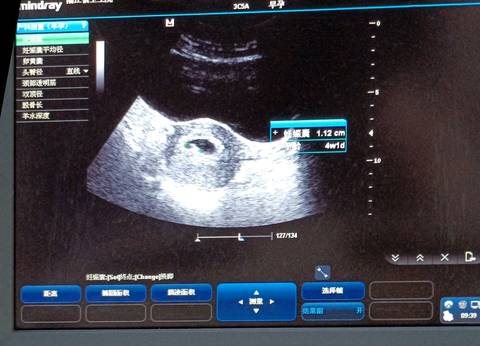

听说孕囊可以看出男孩女孩 大家帮忙看看

journal_insert_pic_1686145080

通过这些是看不出来的,而且也不准确,在怀孕期间,我觉得只要宝宝发育好的话,还是不要想太多了,男孩女孩都一样的。

你好亲爱的,通过这个来判断男孩女孩是不太准确的哈,我们要给他同等的关爱和呵护,也祝你可以如愿以偿,心想事成。